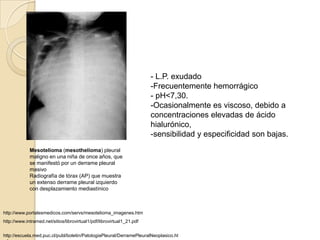

Mesotelioma maligno

Engrosamiento pleural extenso con gruesos

TAC: Afección de pleura mediastínica. Nódulos típicos

- L.P. exudado

-Frecuentemente hemorrágico

- pH<7,30.

-Ocasionalmente es viscoso, debido a

concentraciones elevadas de ácido

hialurónico,

-sensibilidad y especificidad son bajas.

Mesotelioma (mesothelioma) pleural

maligno en una niña de once años, que

se manifestó por un derrame pleural

masivo

Radiografía de tórax (AP) que muestra

un extenso derrame pleural izquierdo

con desplazamiento mediastínico